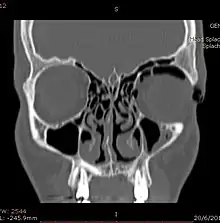

CT scan taken from the coronal plane demonstrating orbital emphysema.[39]

Computed tomography is effective and sensitive in the diagnosis of orbital emphysema,[3][37] as it can confirm the anatomical location and size of air, bony defects, indentation of the eyeball, and the condition of the optic nerve, as well as the presence of any extraocular muscle entrapment and herniation of preorbital fat into the sinus cavities.[3][15][38] The location of the orbital emphysema is present near the site of the fracture.[1][3] The scans are usually taken along the transverse plane. Transverse images allow the evaluation of fractures in medial and lateral orbital walls. By reformatting these transverse images or taking coronal images, the examination of orbital floor and roof is permitted. Helical scanning is preferred as it has a lower imaging time and radiation dose comparing to conventional scanning, especially when reforming transverse helical scans into coronal images.[3] The staging of orbital emphysema can then be determined with visual acuity examination and ophthalmoscopy.[6] A disadvantage of using a CT scan is that when detecting air after orbital trauma, the presence of a wooden foreign object can give a false positive result of orbital emphysema. The wooden object can mimic the presence of orbital emphysema. Therefore, patients’ medical history is crucial in making the correct diagnosis.[3]